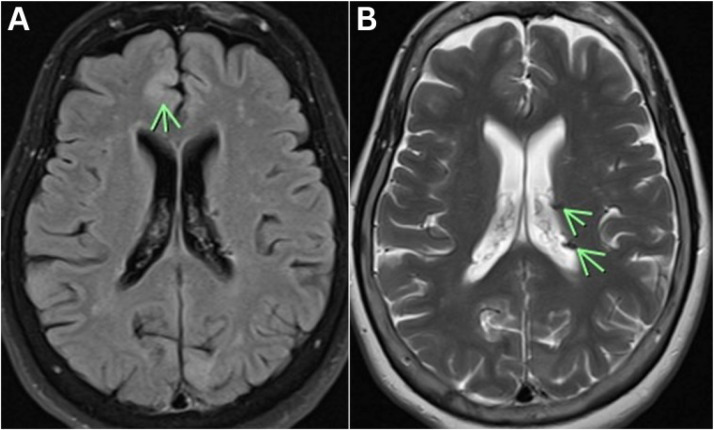

The Multifaceted Nature of Tuberous Sclerosis Complex.